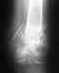

Здравствуйте! Не знаю кому обратиться со своей проблемой и вопросами. Очень надеюсь на Вашу помощь. В пятницу 26 июня 2015 г.(примерно в 14:00) в г. Талица Свердловской области мой отец 51 год упал с крыши второго этажа, выполняя монтажные работы. При падении получил 3 перелома: перелом пятки, локтя и открытый перелом бедра. Был госпитализирован в районную больницу г. Талицы.

Была оказана первая помощь. Ему сделали снимок, растянули, вставили штыри в бедренную кость, зашили рану и обезболили. Врачи сказали, что оперировать они его не могут, от выписки направления и транспортировки в Екатеринбург тоже отказались, сославшись на пятницу, отсутствие транспорта, отсутствие анализов, без которых в Екатеринбурге не примут. Анализы обещали взять в понедельник. За выходные поднялась высокая температура 38-39,5, ноги сильно отекли. (Особенно надулась нога где был открытый перелом). В палате очень жарко. Наступил понедельник. Температура не спадает. Анализы взяли. Утром на обходе пришел врач и без обезболивания раскрыл рану на бедре,был поставлен дренаж. Пошел гной. Выписали антибиотики. От выписки направления и транспортировки опять отказались, сославшись уже на гной, отеки и воспаление, с которыми нас в Екатеринбург не примут. По уже имеющимся инцидентам в г. Талица, когда направления в Екатеринбург выписывают слишком поздно, а лечиться за деньги нет возможности, я очень опасаюсь за здоровье моего отца. Хотела бы спросить, когда в таких случаях ожидать направления в Екатеринбург, транспортировки и операций? Есть ли риск для здоровья отца в такой ситуации?